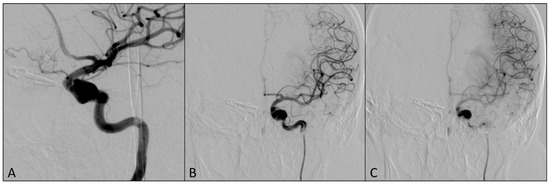

2. Case Report